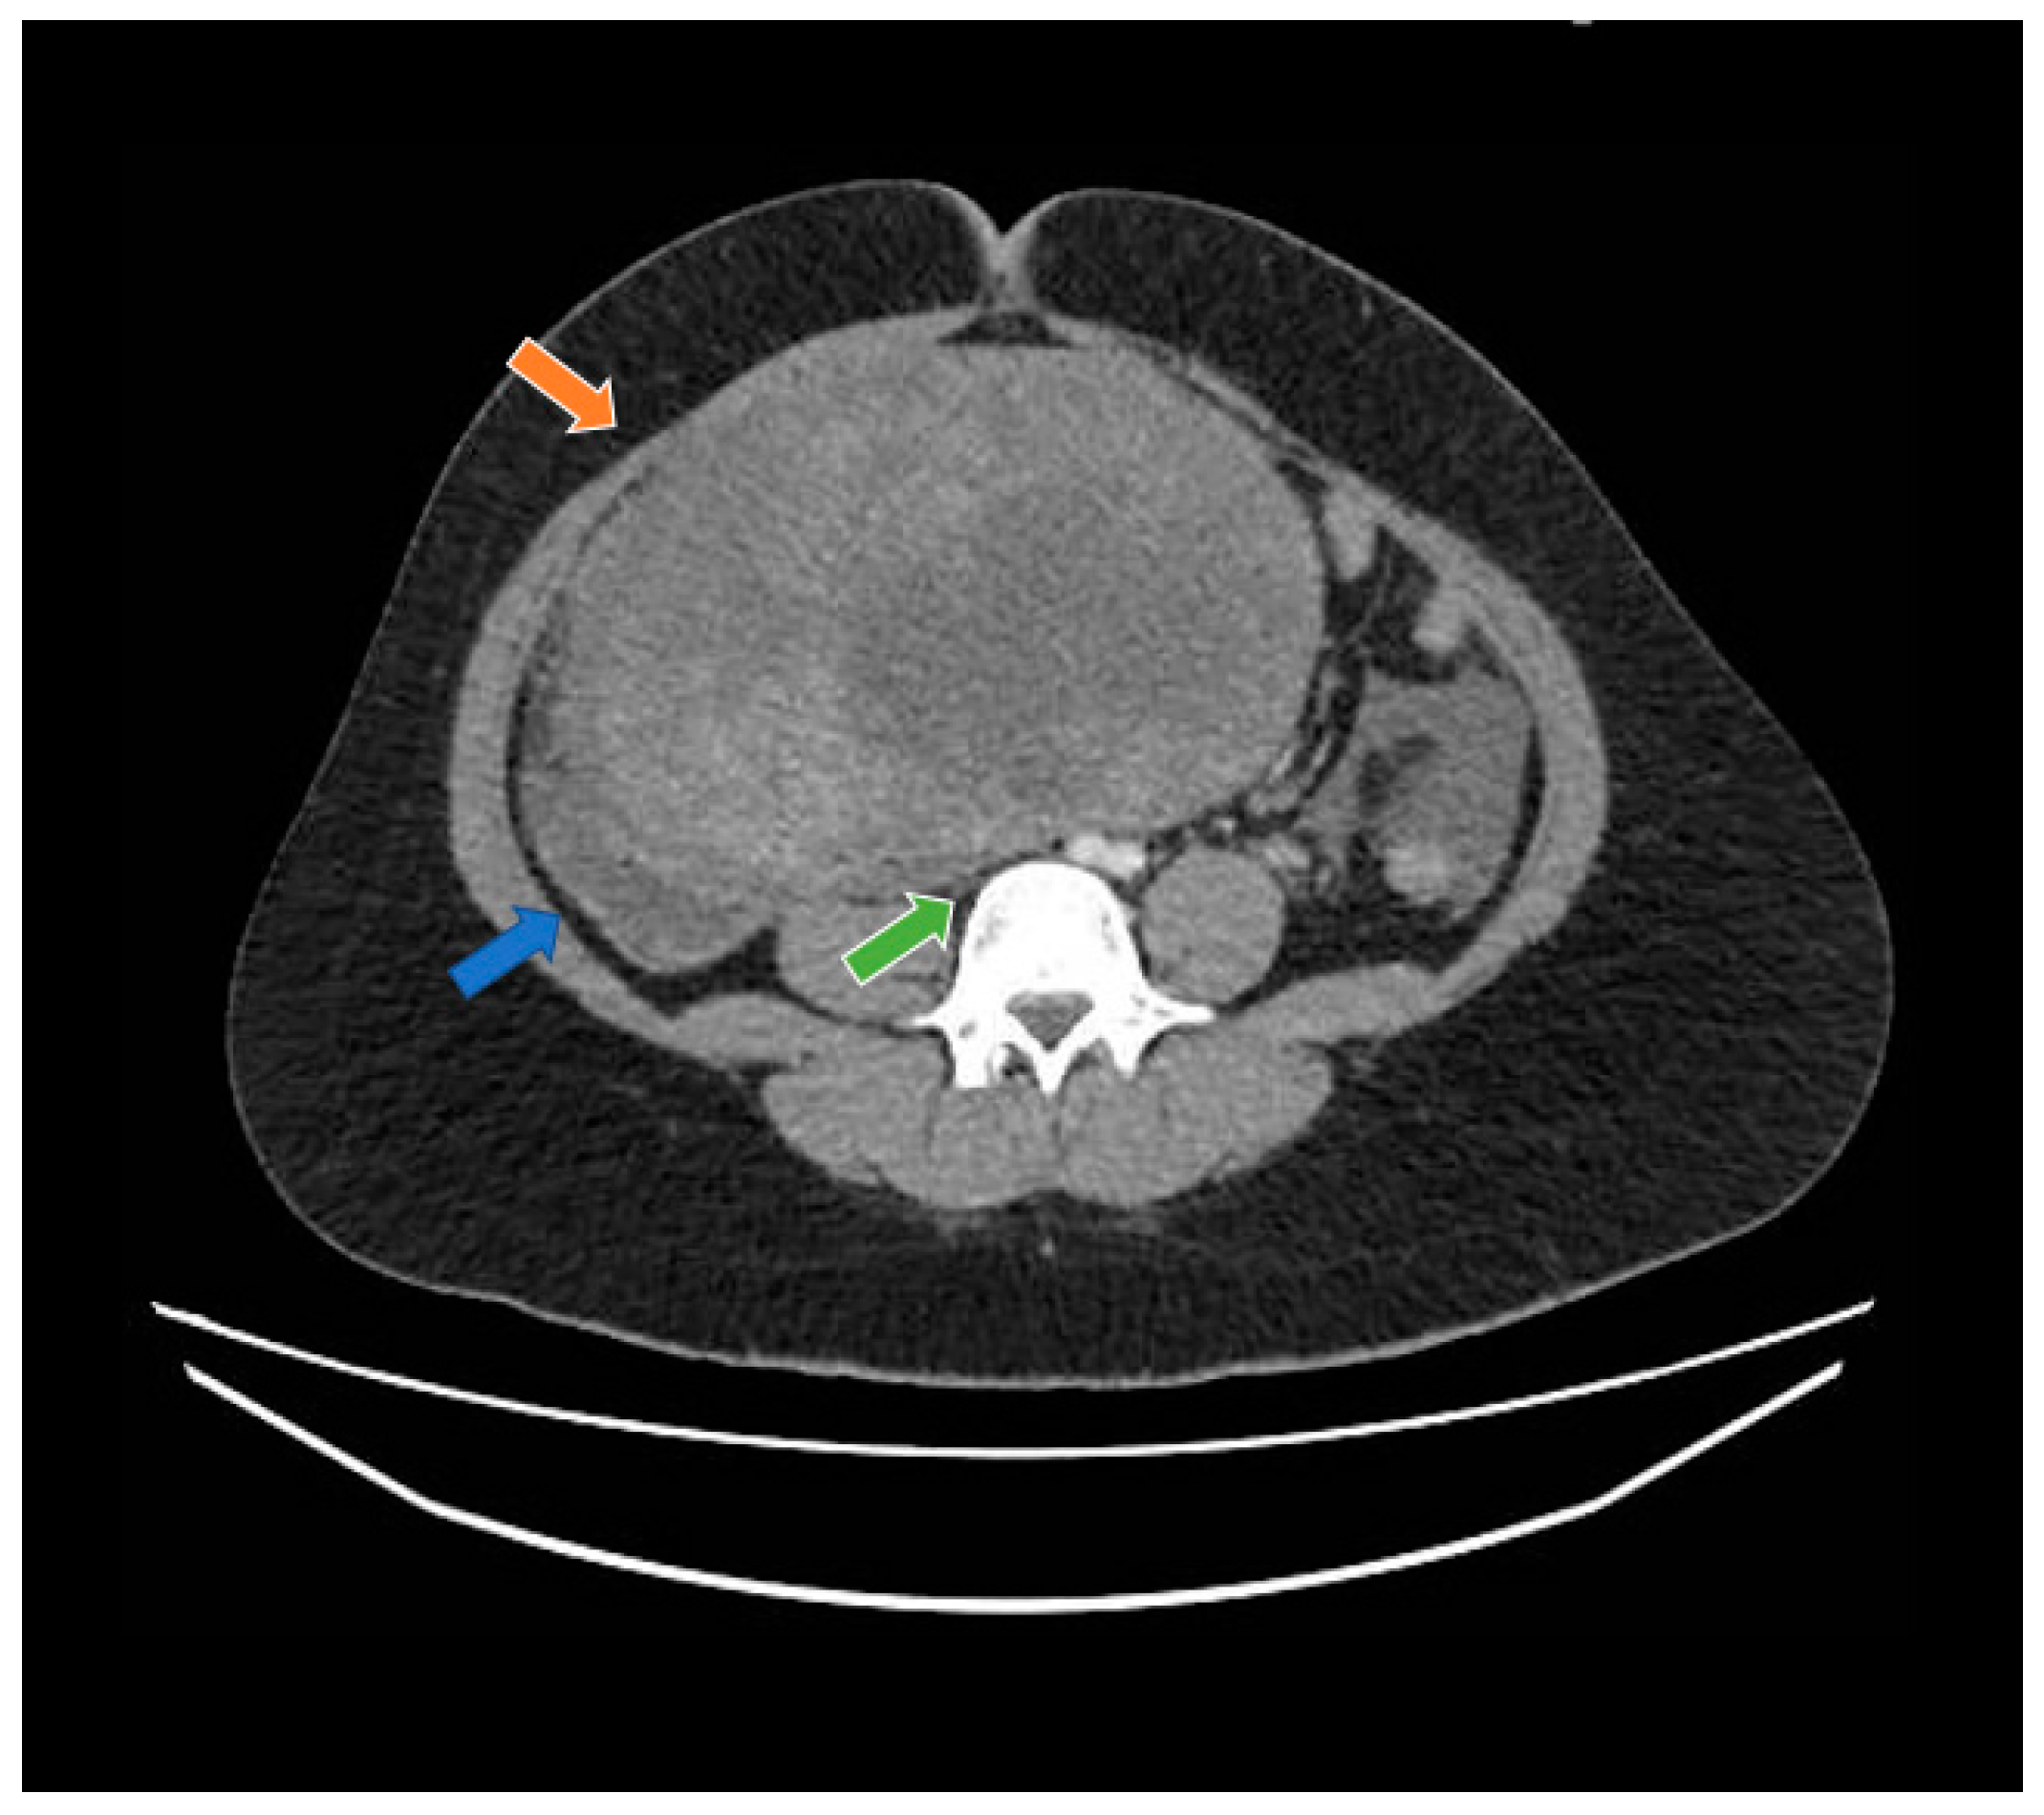

A 19-year-old woman with neither comorbidities, previous pregnancy history, nor a personal or family history of cancer was referred to our healthcare service in February 2020 due to abdominal pain and swelling that had started two weeks earlier. Before starting her diagnostic investigation, the patient signed an agreement allowing the use of her clinical, radiological, and pathology information for clinical research; after that, the clinical investigation began. A physical exam uncovered a mass in the right iliac fossa topography. An abdominal computed tomography scan and magnetic resonance imaging showed a large abdominopelvic mass located on the flank and right iliac fossa, measuring 228 mm × 188 mm × 143 mm (CC × LL × AP)—Figure 1 and Figure 2, respectively. This mass occupied the mesogastrium and compressed the internal iliac vessels and the psoas, with no clear separation plane among them. The images also showed moderate ascites and retroperitoneal lymph nodes forming clusters. Initial laboratory tests showed a normal value of ionic calcium (1.3 mmol/L).

Figure 1.

Computed tomography study in the portal phase showing a heterogeneous mass in the pelvic region (orange arrow), displacement of the intestinal loops to the right (blue arrow), and compression over the inferior vena cava (green arrow).